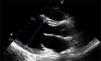

Caso clínicoAdolescente de 14 anos, sexo feminino, com antecedentes pessoais de enxaqueca hemiplégica e quisto pineal, submetida a ressonância magnética (RM) cranioencefálica de controlo. Durante a indução anestésica com propofol verificou‐se bradicardia, revertida com atropina, seguida de taquidisritmia ventricular, revertida com lidocaína e murro pré‐cordial. Nas primeiras horas de internamento evoluiu para edema pulmonar (Figura 1) associado a insuficiência respiratória global (SaFi 156, PCO2 57mmHg) e hipotensão (89/56mmHg, PAS e PAD <p5). O ecocardiograma transtorácico mostrou dilatação do ventrículo esquerdo com hipocinesia global envolvendo todos os segmentos meso‐basais, mas poupando o ápex, condicionando compromisso moderado a grave da função sistólica global do ventrículo esquerdo e fração de ejeção reduzida (<30%) (Figuras 2 e 3). O eletrocardiograma (ECG) revelou taquicardia sinusal persistente e alterações inespecíficas do segmento ST em V4 e V5 (Figura 4). Os biomarcadores cardíacos encontravam‐se elevados (CK total 217UI/L, troponina I 2,42ng/ml, pro Peptido Natriurético Cerebral [proBNP]) 8284pg/ml). Foi medicada com diuréticos e captopril, havendo necessidade de terapêutica com dopamina para otimização da função renal (máximo 2mcg/kg/min) e digoxina nas primeiras 24h. Foram realizados ecocardiogramas diários, verificando‐se melhoria clínica e imagiológica nas primeiras 48h e recuperação completa da função sistólica do ventrículo esquerdo em D4. Os valores dos biomarcadores cardíacos diminuíram ao longo dos primeiros dias (troponina I 0,69ng/ml em D2 e 0,44ng/ml em D3; proBNP 2842pg/ml em D3) com normalização em D6 dos valores de CK I total e troponina I e descida significativa do proBNP (329pg/ml). Suspendeu diuréticos em D9 e teve alta medicada com carvedilol. A RM cardíaca não mostrou alterações, nomeadamente cicatriz de miocardite ou enfarte, tendo suspendido terapêutica com carvedilol. Da investigação realizada salienta‐se função tiroideia normal e serologias virais (CMV, EBV, HSV 1, HSV 2, HSV 6, parvovírus, adenovírus, influenza A e enterovírus) negativas. Manteve acompanhamento regular em consulta de cardiologia pediátrica.

Relativamente à apresentação ecocardiográfica, pode apresentar‐se sob a forma clássica de STT (com balonamento apical e envolvimento do segmentos apical ou mesoapical) ou forma invertida (com envolvimento dos segmentos meso, basal ou mesobasal)3. O caso acima descrito enquadra‐se nas formas invertida ou global, ambas descritas em idade pediátrica3.